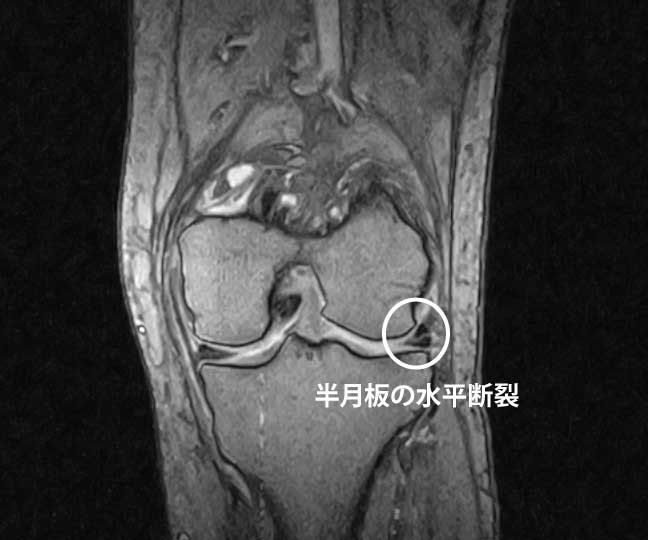

MRIで半月板損傷が写っても=痛みの原因とは限らない。

中高年では無症候の半月板損傷は珍しくありません(画像所見と痛みは一致しないことが多い)。 -

年齢とともに半月板には**退行性変化(スジや裂け目)**が入ります。痛みがなくてもMRIで損傷が見つかることは珍しくありません。